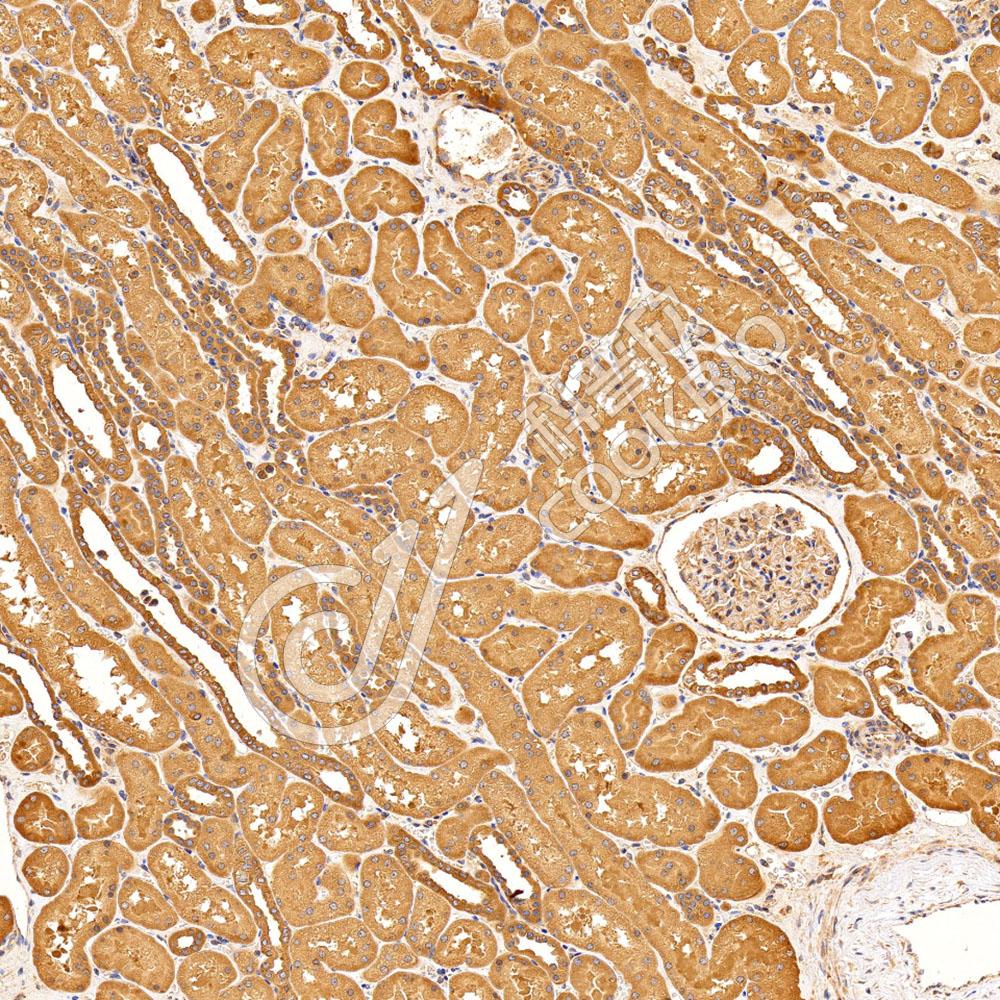

图像

WB检测Histone H3.

3蛋白(货号 K133078).

样品: 经RIPA裂解液(货号KSG2002)处理的蛋白质.

封闭: 3%脱脂牛奶(货号KSGC310001)溶于TBST溶液, 室温孵育1小时.

—抗: 1: 500稀释, 4℃ 孵育过夜.

二抗: HRP标记山羊抗兔IgG (H+L) (货号KB69909), 1: 5000稀释, 室温孵育1小时.